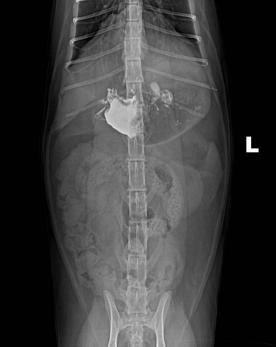

c.X线检查。对于阻线性较强的物质(如金属、骨头)较容易辨别,对于阻线性与组织密度相似的物体较难确定,但是可以通过消化道灌服造影剂判断是否有阻塞或可包裹物体。

机械性肠梗阻的读片要点:1.体积增大;2.形态轮廓变化;3.影像密度变化;4.浆膜细节变化。

金毛 线性异物